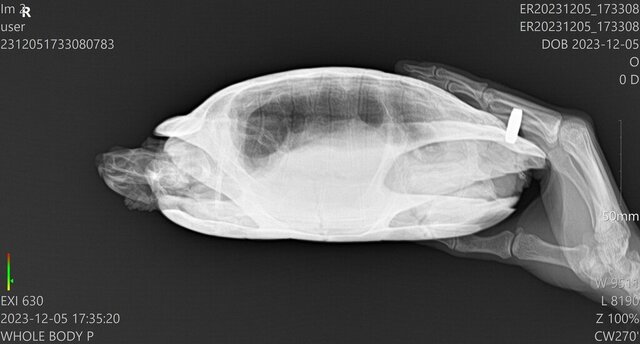

Сделали рентген, предварительный диагноз - пневмония. Укололи Энроксил и Элеовит, через час черепаха очень вялая была, спала, на прикосновения не реагировала, но к утру активность вернулась

Не могли бы вы посмотреть рентген и назначения? Хотелось бы убедиться, что можно продолжать лечение   по этой схеме857955925_WhatsAppImage2023-12-06at09_16_05.thumb.jpeg.5e6ec42bf0c6add2ebb8df78cf6187ff.jpeg1540015184_ER20231205_173308_ER20231205_173308__05-12-202317_38_49_1-3(1).thumb.jpg.599338906b0ed89dfb86f8237ae1f926.jpg1270917588_ER20231205_173308_ER20231205_173308__05-12-202317_35_20_1-2(1).thumb.jpg.5b554520fd66f625d542af4cb855f73d.jpg

@Zefa по снимкам да, лёгкие мутные

Назначения Вам сделали правильные и по дозировкам и по препаратам. После укола черепаха вялая - это реакция на антибиотик, т.к. дозировка для режима через день. Если ей прям так плохо после укола, то можете колоть 0.11мл, но каждый день, начиная со дня, когда нужно следующий укол делать.